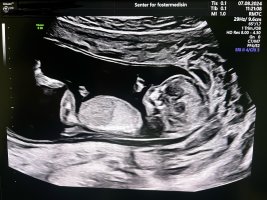

Åh det er en fantastisk følelseHer er lille gullet vårt ved gårsdagens ultralydTermin ble satt en dag frem, med andre ord ganske godt beregnet menstermin

Er da 13+0 i dag, men tenker jeg fortsatt tar mest utgangspunkt i menstermin, det blir minst forvirrende. Jeg var så redd på forhånd, dette var aller første UL bortsett fra en sjekk JM gjorde i uke 8 på et veldig dårlig og lite UL apparat. Heldigvis var det ingenting å bekymre seg for, og alt er i skjønneste orden med lille

Jeg ble mildt sagt lettet med x antall kilo

Jordmor sa at de ikke kunne si noe om kjønn så tidlig, og helt ærlig brydde jeg meg bare om at alt var bra. Da har vi noe å glede oss til ved neste UL

Men er det noen som vil prøve å gjette kjønn?